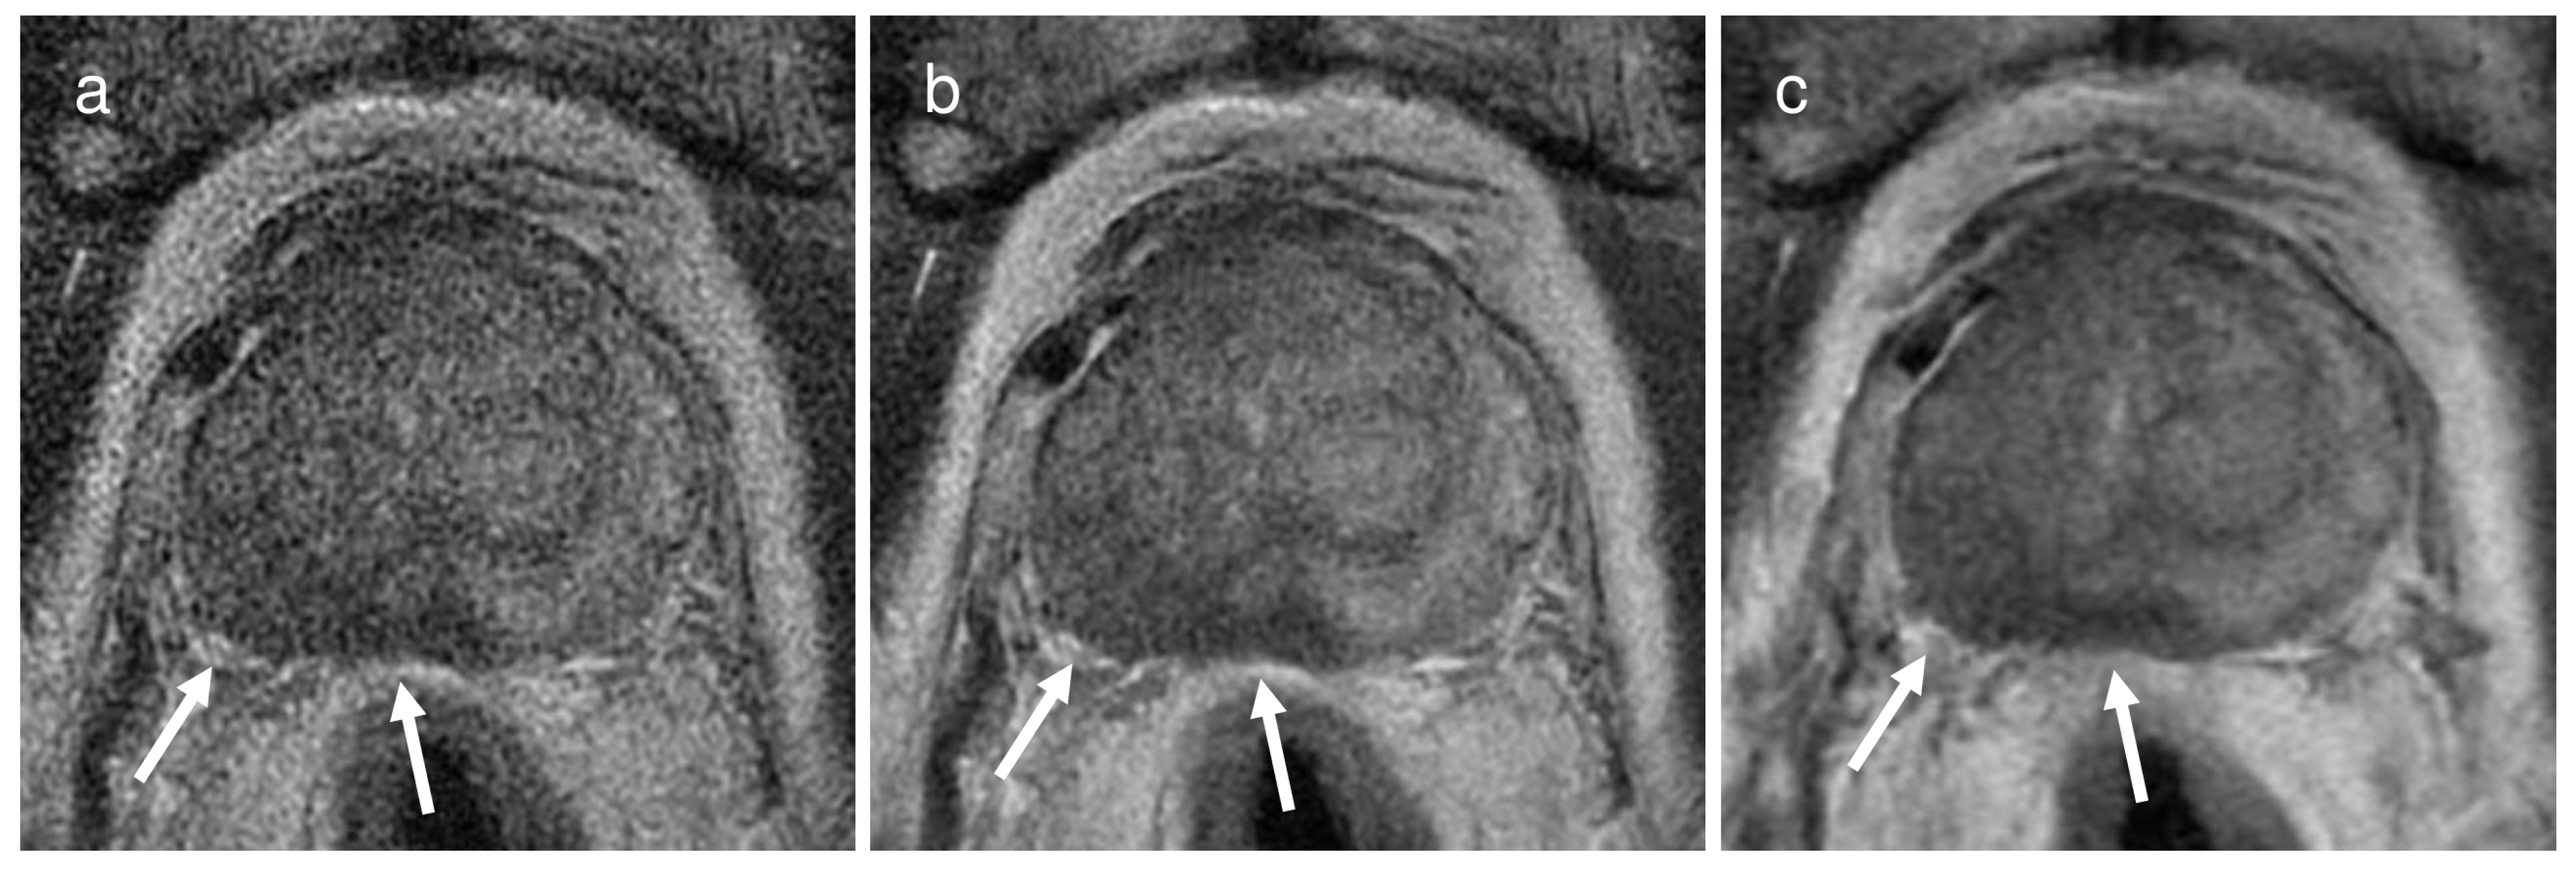

Figure 2.

A representative case of a 74-year-old man with a Gleason score of 9 in the right middle peripheral zone demonstrating extra-prostatic extension through the right posterolateral capsule (arrows) on (a) a 2 mm thin-slice T2WI without deep learning reconstruction (DLR), (b) the same 2 mm T2WI with DLR, and (c) conventional T2WI with 3 mm slice thickness. For both reviewers, the confidence score for presence of extra-prostatic extension increased from 4 (probably present) on the 2 mm thin-slice T2WI with or without DLR to 5 (definitely present) on conventional T2WI.